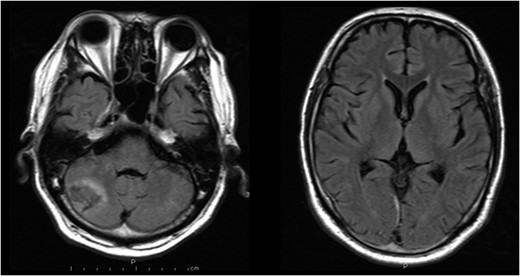

A 48-year-old man was admitted to our hospital because of loss of consciousness after a sudden nuchal pain. Brain computed tomography (CT) showed diffuse SAH (Fig. 1A). The following CT angiogram showed a fusiform aneurysm at the right vertebral artery with contralateral hypoplasia (Fig. 1B). The endovascular procedure was performed under general anesthesia. The patient received a loading dose of 200 mg of aspirin and 300 mg of clopidogrel via a nasogastric tube. A preoperative angiogram showed VAD with a blister at the pseudolumen (Fig. 2A). Initially, a stent (Enterprise, 4.5 mm × 37 mm; Codman, Raynham, MA, USA) was deployed from the basilar artery to the right vertebral artery. A second stent (Enterprise2, 4.0 mm × 30 mm) then overlapped the first stent, covering the pseudolumen (Fig. 2B). Coiling was performed from a microcatheter (Excelsior SL-10/45; Boston Scientific, Fremont, CA, USA), which was jailed in the pseudolumen. After the first coil perforated the blister, a balloon catheter (Scepter C, 4.0 mm × 15 mm; Microvention, Tustin, CA, USA), which was exchanged with a stent delivery catheter, was inflated in the stent. All five small platinum coils (Target nano, 2 mm × 4 cm and 1.5 mm × 2 cm; Stryker, Fremont, CA, USA) completely occluded the pseudolumen (Fig. 2C), and the right vertebral artery was preserved (Fig. 2D). Magnetic resonance imaging, which was obtained 3 weeks after the procedure, showed right cerebellar infarction without damage of the brainstem (Fig. 3). The patient recovered and returned to his former job after 2 weeks of intensive care and 3 months of rehabilitation therapy. An angiogram, which was obtained 6 months after procedure, showed no recurrence of VAD (Fig. 4).

Magnetic resonance images obtained 3 weeks after the procedure shows right cerebellar infarction without damage of the brainstem.